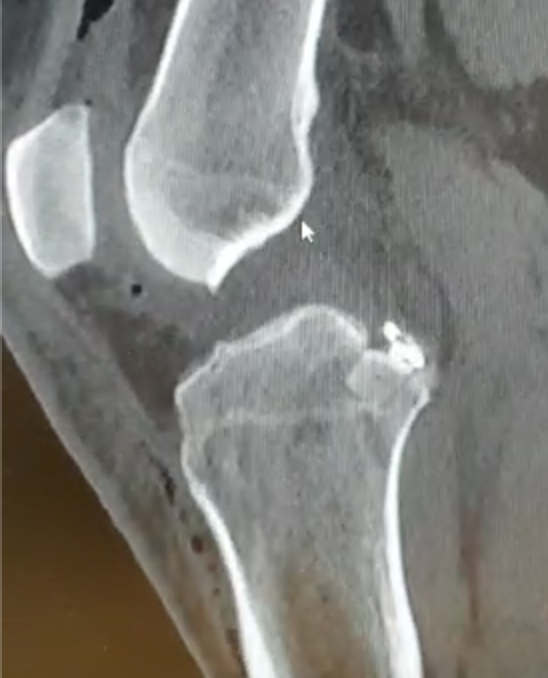

- MRI evidence of tibial / femoral peel off

- consider acute repair

Acute femoral peel off of PCL

Acute repair of femoral peel off with suture tape augmentation

Indication

Femoral avulsion of the PCL

Acute injury

Technique

Repair to PCL to femoral insertion with sutures

Pass suture tape through tibial insertion to femoral insertion PCL to augment